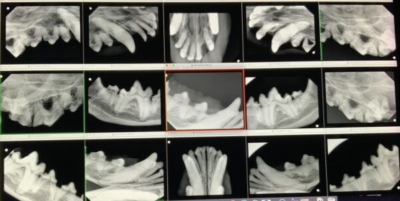

まず、全身麻酔をかけて歯科レントゲンを全ての歯で撮影します。

上顎切歯

上顎の切歯のレントゲン

黄色斜線部分が歯の周りの骨が溶けてしまったところ。

このようにひとつひとつの歯を評価していきます。